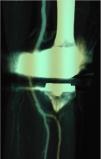

ResultadosEntre octubre de 1979 y octubre del 2016 se atendieron 74 traumatismos de arteria poplítea, de los que 10 estuvieron relacionados con cirugía ortopédica (13,5%). Durante ese periodo se realizaron 7.400 intervenciones ortopédicas (10/7.400), lo que representa un 0,1%. En 4 ocasiones fueron secundarias a prótesis total de rodilla, en 2 a refracturas de fémur, en 2 a cirugía correctora de tibia vara, uno a desepifisiodesis y uno a cirugía de un osteosarcoma. La clínica fue de isquemia aguda en 5 casos, hemorragia en 2 casos y falso aneurisma en 3 casos, asociándose una fístula arteriovenosa en uno de los casos de fractura (fig. 1) (tabla 1). La mediana de edad fue 43 años (fig. 2), con 3 en edad pediátrica, 2 menores 60 años y 5 entre 60-80 años. Fueron necesarias 6 arteriografías (figs. 3 y 4), y 2 angio-TAC (fig. 5). La reparación fue inmediata (0-12 h) en 3 pacientes, entre 12-24 h en un paciente y superior a 24 h en 6 ocasiones. Todas fueron abordadas por vía medial, siendo la reparación mayoritaria la vena safena (3 ocasiones con injerto venoso) (fig. 6). Otras técnicas fueron: la interposición protésica en 2 pacientes, la sutura simple en 2 casos y la angioplastia con parche autólogo en un paciente. Durante este periodo se observaron 3 síndromes compartimentales secundarios a la iatrogenia poplítea que precisaron de fasciotomías. En 2 ocasiones fue necesaria una amputación, una de ellas en un paciente con patología arterial previa y otra directa por lesiones irreversibles. Ambas correspondieron a pacientes con reparación tardía. La capacidad funcional quedó manifiestamente alterada en 4 pacientes: 2 por amputación mayor y 2 por lesión de nervio ciático poplíteo externo.

| 5 | 43 | Refractura | Masa pulsátil | > 24 | Arteriografía | FA + FAV | Bypass poplíteo-poplíteo | Permeabilidad | No | – |